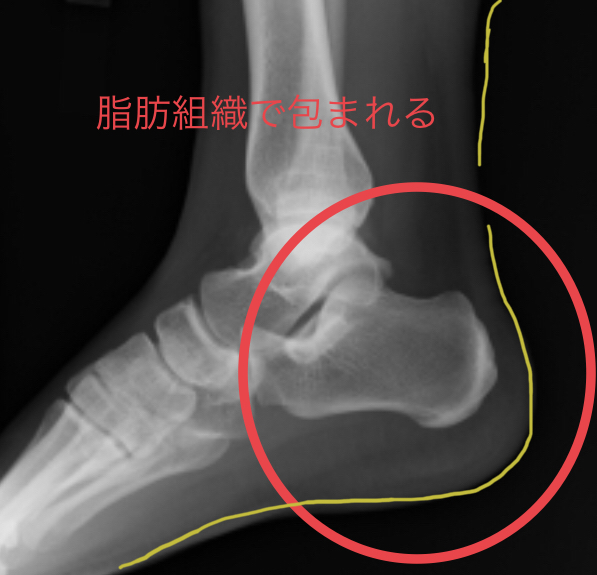

かかとと言われる部分の骨は踵骨(しょうこつ)です。

骨にはアキレス腱・足底筋膜(腱膜)・屈筋支帯など

筋肉や筋膜の延長部分となる腱と呼ばれているものが付着しています。

腱は骨のほんの一部に存在しているだけで

かかとの骨を包みこむ多くの面積を占めているのは脂肪です。

(詳しくは写真を参考に)